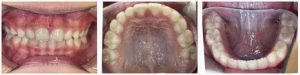

▼ Before(治療前)

◆ 治療の流れ(2021年8月〜2023年8月 / 約24ヶ月)

2021年8月〜2023年8月(約24ヶ月)

拡大床によるスペースづくり

治療開始から数ヶ月は、上あごの幅を段階的に広げ、永久歯が並ぶためのスペースをつくりました。